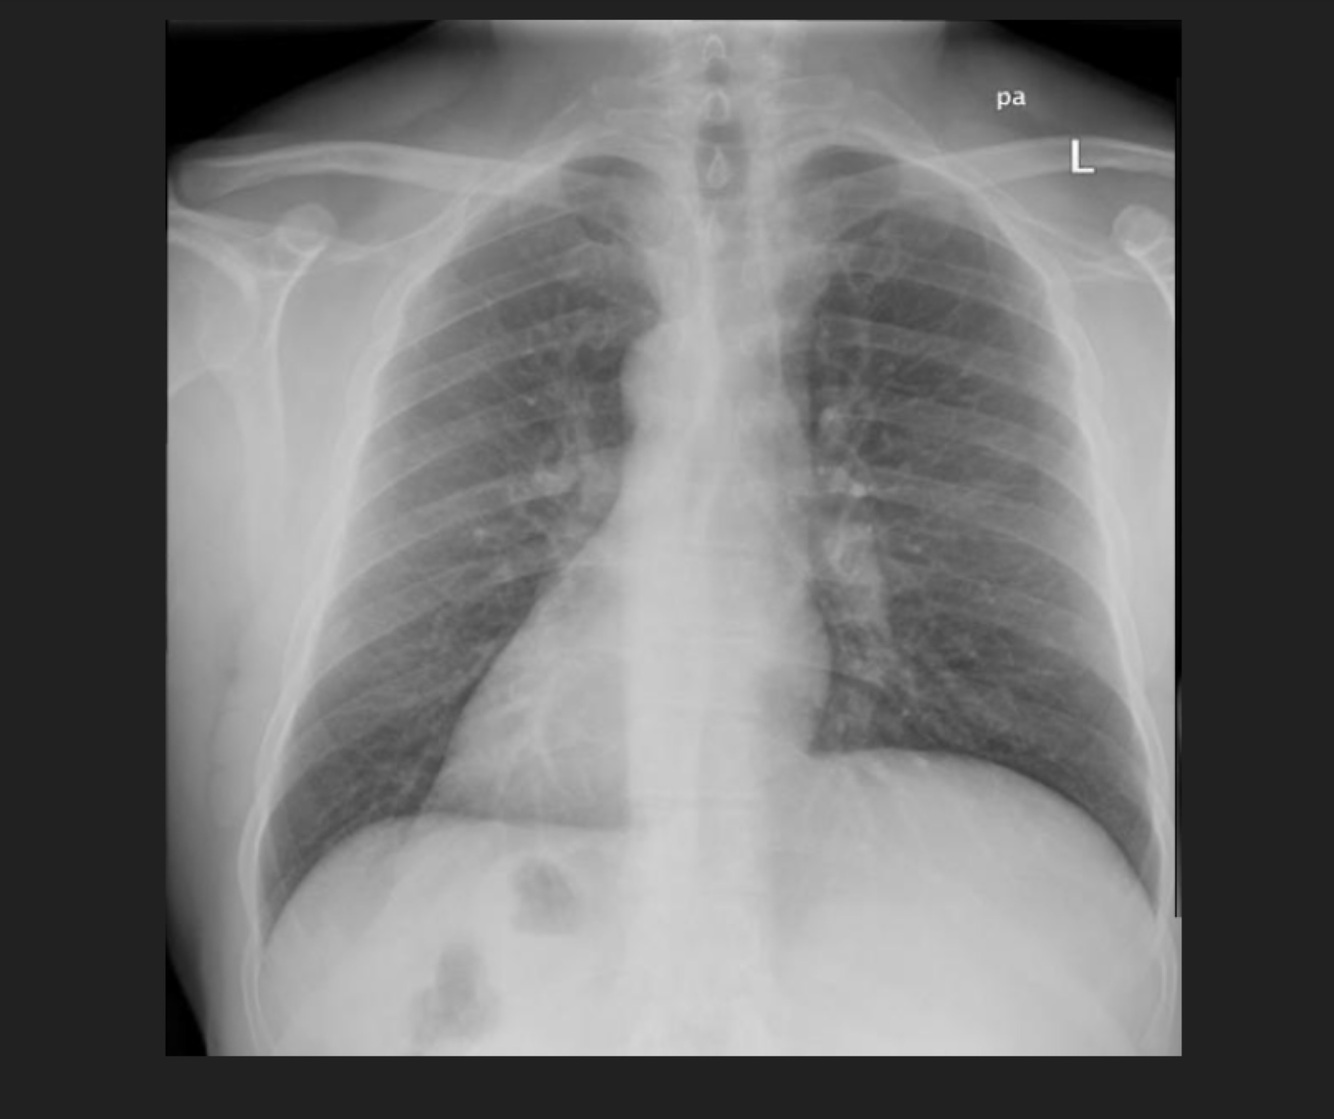

Q

Masculino de 66 años de edad, cuenta con el diagnóstico de VIH positivo, con fiebre, disnea

A

TB Miliar